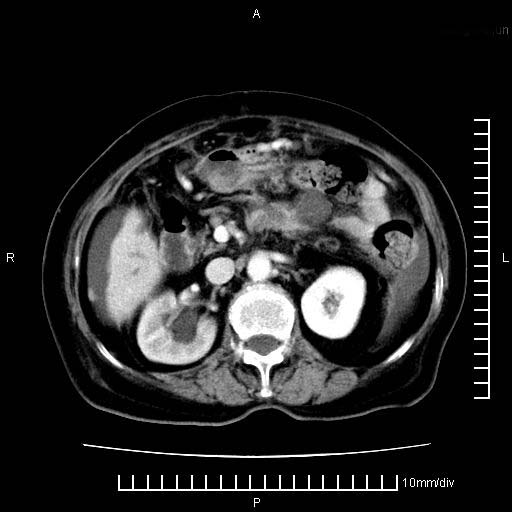

标题: CT28280:腹部增强:女性,80岁

上腹疼痛月余,外院核磁诊断胰腺癌。现临床示右下腹可明显触及包块,可片子上怎么没有看到?

1.胰腺颈体部癌。

胰腺体部癌累及周围器官,腹膜、粘连

1。胰腺ca伴腹膜腔转移

2。肝左叶低密度灶,考虑转移可能

胰腺体部癌累及周围器官,腹膜、粘连,临床摸到的可能是粘的组织

胰腺结构模糊,胰尾部见囊性包块,周围脂肪密度增高,左肾前筋膜增厚,胸水、腹水。不符合胰腺ca伴腹膜腔转移。考虑胰腺炎伴假性囊肿形成、胸腹腔积液。

1)考虑胰腺癌并胰腺假性囊肿形成。2)肝内低密度灶,不排除转移。3)右肾盂积水。4)腹水。5)右侧胸腔积液并右肺下叶部分膨胀不全。

考虑胰腺ca伴腹膜腔转移、肝左叶转移、右肾积水。右胸腔积液。